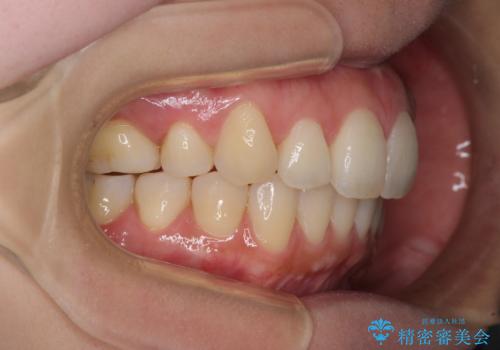

再矯正で突出した口元を引っ込める 抜歯矯正の後戻り

- 抜歯矯正の後戻りで前歯が突出してきていることを気にして来院された患者様です。

口元の突出感を改善するにあたり、抜歯矯正は行うことができないため、奥歯の後方移動とIPR(歯と歯の間を削る)により達成することとしました。

再度後戻りしたときに対応しやすいよう、インビザラインにて矯正治療を行うこととしました。

しっかりと装着時間を守り、ゴムかけにも協力していただいたので、口元を引っ込めることができました。